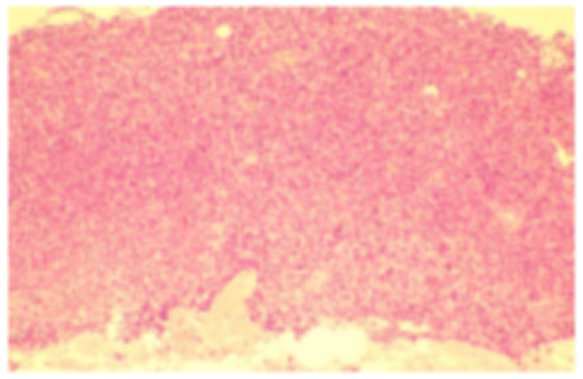

骨髓细胞学检查示(2024-11-07):淋巴细胞比例增加,其中形态异常淋巴细胞占76.5%,形态:胞体大、胞浆量多少不一,少数胞浆可见空泡,核型不规则,可见折叠、扭曲或切迹,核染色质聚集不一,可见团块状,部分细胞可见核仁。诊断意见:考虑淋巴瘤骨髓浸润,请结合免疫分型。

图2. 骨髓细胞形态学表现

骨髓活检+免疫病理示(2024-11-11):镜下HE及PAS染色示送检骨髓增生明显活跃(60%-70%),异常B淋巴细胞增多(70%-80%),胞体中等至大,胞浆量中等。粒红系细胞少,散在分布。巨核细胞少。网状纤维染色(MF-2级,灶性)。补充免疫组化:CD5(+),CD20(+),CD23(+),PAX5(+),CD3(-),Cyclin D1(-),SOX11(-),CD138(-),LEF1(+),CD10(-)。诊断意见:慢性淋巴细胞白血病治疗后,骨髓增生明显活跃,异常B淋巴细胞多见,胞体偏大,请结合临床及相关检测。

图3. 骨髓活检病理表现